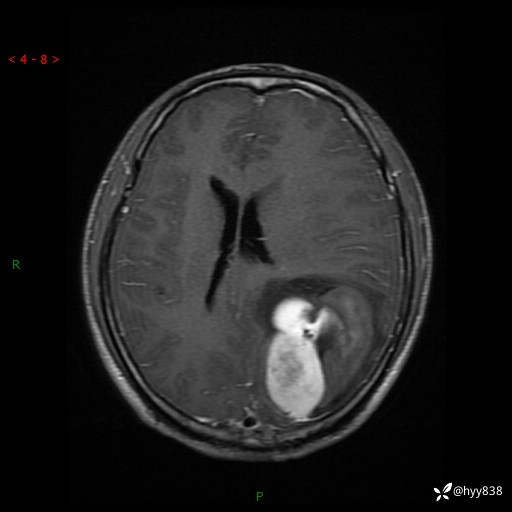

病例年轻小伙,头痛伴呕吐半年,渐进性加重1月。疑难病例,第一次见--结果公布~

性别:男

年龄:21岁

简要病史:头痛伴呕吐半年,渐进性加重1月

颅脑MRI平扫+增强